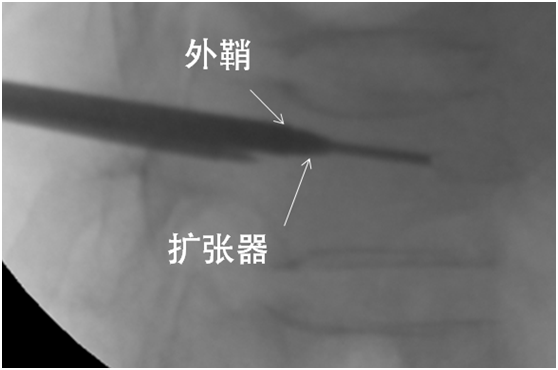

引导丝指引

取出针芯置入引导丝。

取出穿刺针外管沿引导丝放置工作通道:外鞘过椎体后缘3-5mm。